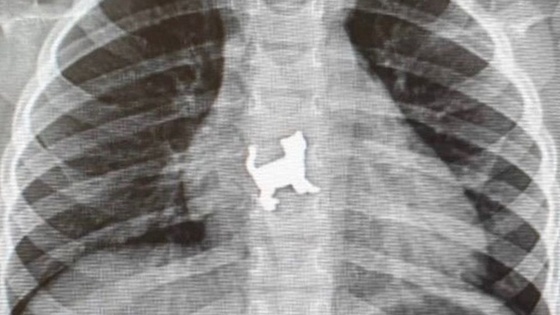

Ее привезли в Республиканскую детскую клиническую больницу с жалобами на боли в грудной области. Родители сказали, что во время игры малышка случайно проглотила металлическую игрушку в форме кошки. В экстренном порядке хирурги провели ригидную эзофагоскопию и удалили инородное тело.